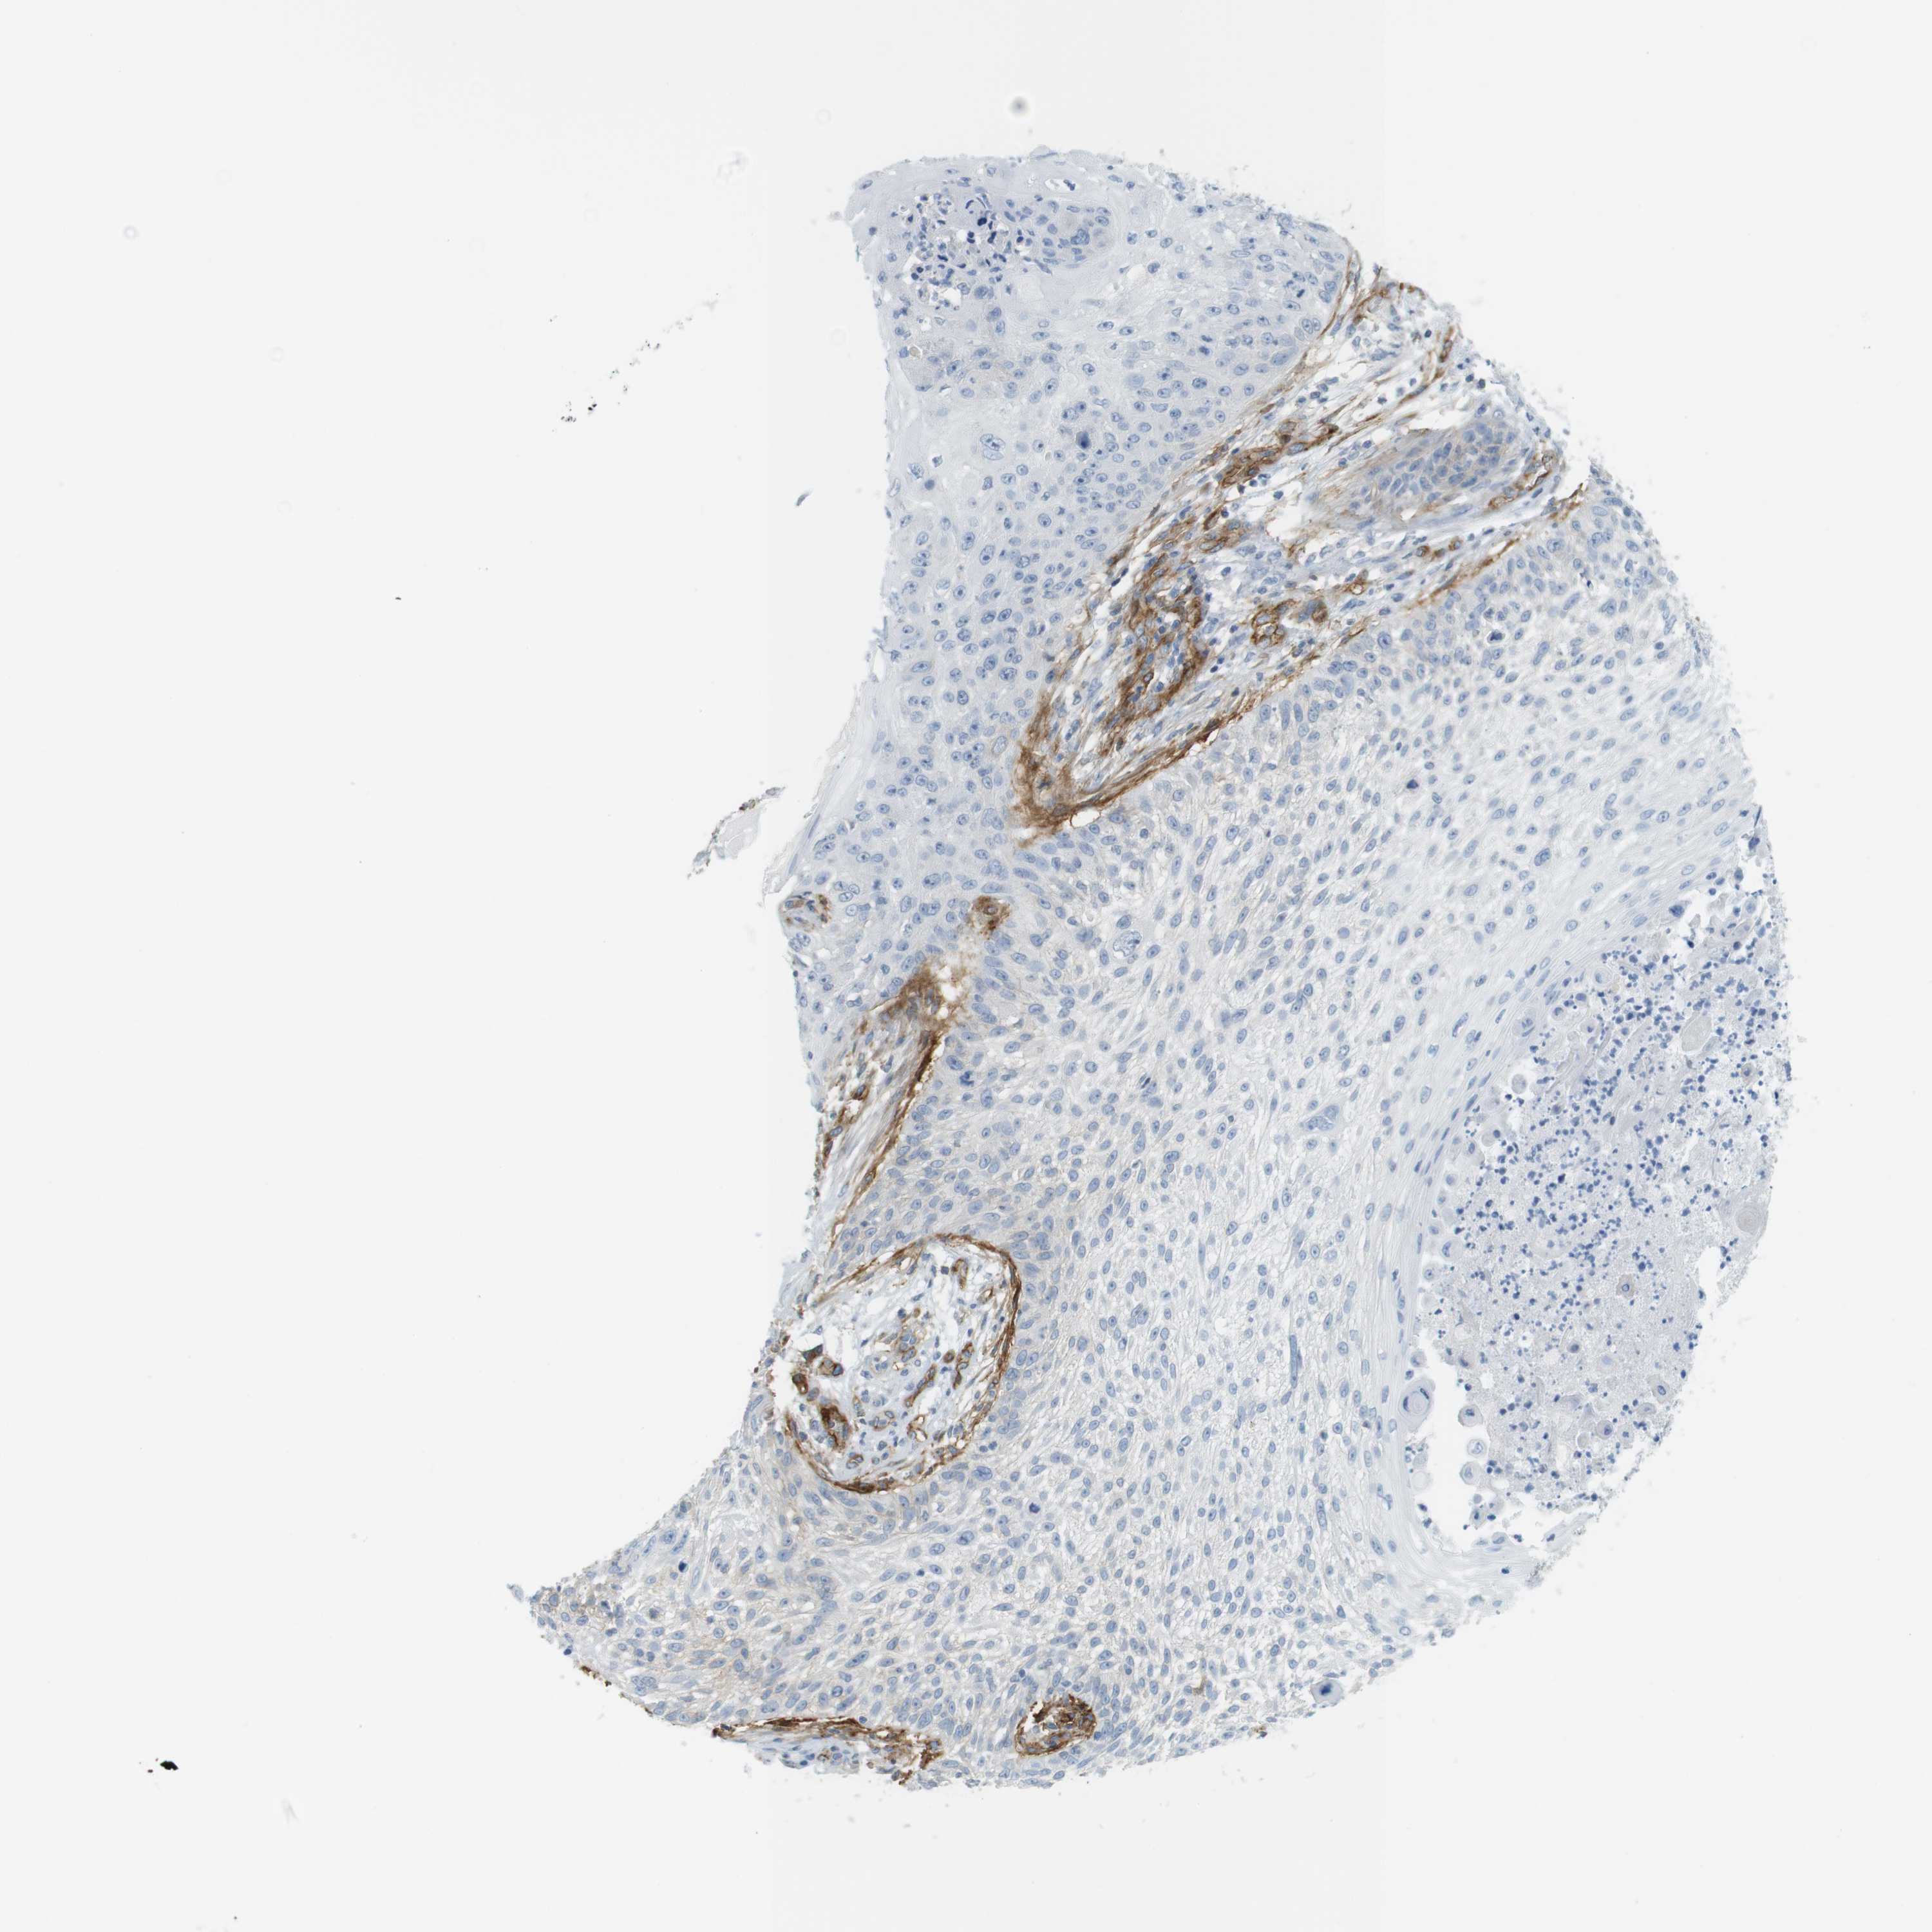

Basal cell and squamous cell cancer

SKIN CANCER - Protein expressioni

A mouse-over function shows sample information and annotation data. Click on an image to view it in a full screen mode. Samples can be filtered based on level of antibody staining by selecting one or several of the following categories: high, medium, low and not detected. The assay and annotation is described here.

Each image is clickable and will lead to virtual microscopy that enables deeper exploration of all samples and also displays staining intensity scores, fraction scores and subcellular localization as well as patient and tissue information for each sample.

Antibody CAB008973

Staining

Not detected

Moderate

Negative

>75%

None

Cytoplasmic/membranous

Squamous cell carcinoma, NOS

Basal cell carcinoma

Squamous cell carcinoma in situ, NOS